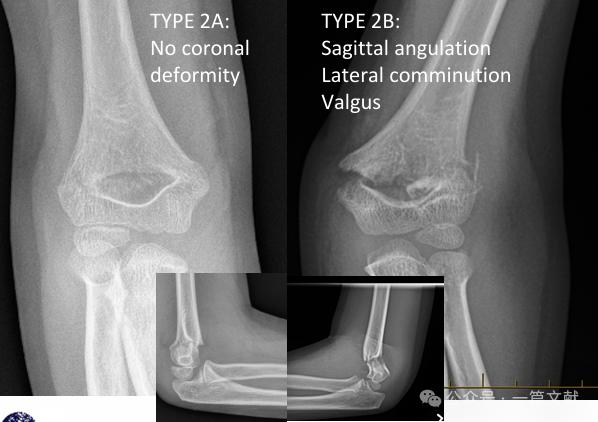

* Modified Gartland Classification:

* Type 2A: Sagittal plane angulation only. Suitable for closed reduction and long arm casting, requiring close follow-up.

* Type 2B: Fracture with rotational, coronal plane angulation (varus, valgus), and/or translational components. May be associated with comminution or impaction. High failure rate with closed reduction alone (without percutaneous pinning). Closed reduction and percutaneous pinning (CRPP) is recommended.